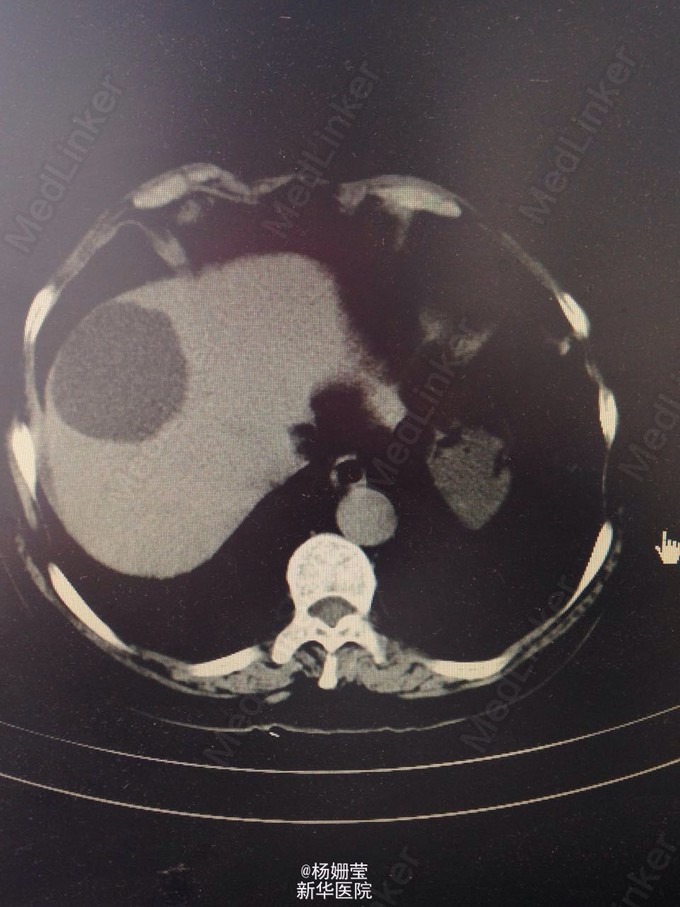

女,46岁。 主诉:两天内黑便五次,伴晕厥一次。 两天日间开始出现解黑便,伴有里急后重感,共解黑便四次,,柏油样尚成形,解便前无腹痛,无恶习呕吐不适,便后无黑朦,胸闷,冷汗等不适,至下午患者休息时突发黑朦,随即晕厥摔倒在地,无外伤。追问病史,患者近两月来时有头晕不适,自觉体力较前明显下降,双下肢乏力,未留意排便颜色便后。 查体神清,气平,双瞳孔等大等圆,对光(+),HR 76次/分,律齐,未及杂音。两肺呼吸音粗,未及明显干湿罗音。腹软伴上腹部压痛,无反跳痛,无肌卫,肝脾肋下未及,肠鸣音减弱。双下肢无浮肿。四肢肌力、肌张力正常,病理征(-)。 辅检:血常规示:血红蛋白 84 g/L|血小板计数 209 10^9/L 头颅CT:右侧侧脑室前角外侧脑梗塞,隐血试验 阳性+++ 诊断:消化道出血;中度贫血 反流性食管炎(LA-B) 肝囊肿 肾囊肿 发热(疟疾待排) 予以抗感染,止血,制酸,流质饮食、维持水电解质酸碱平衡。患者入院后出现发热,咳嗽,给抗感染,发热仍有反复,呈弛张热,予PET检查,高热血找疟原虫,近三日来患者热退,症状好转,要求出院。 随访:出院后患者未行进一步检查。 总结:黑便伴晕厥患者诊断原发病需进行多方面排查。